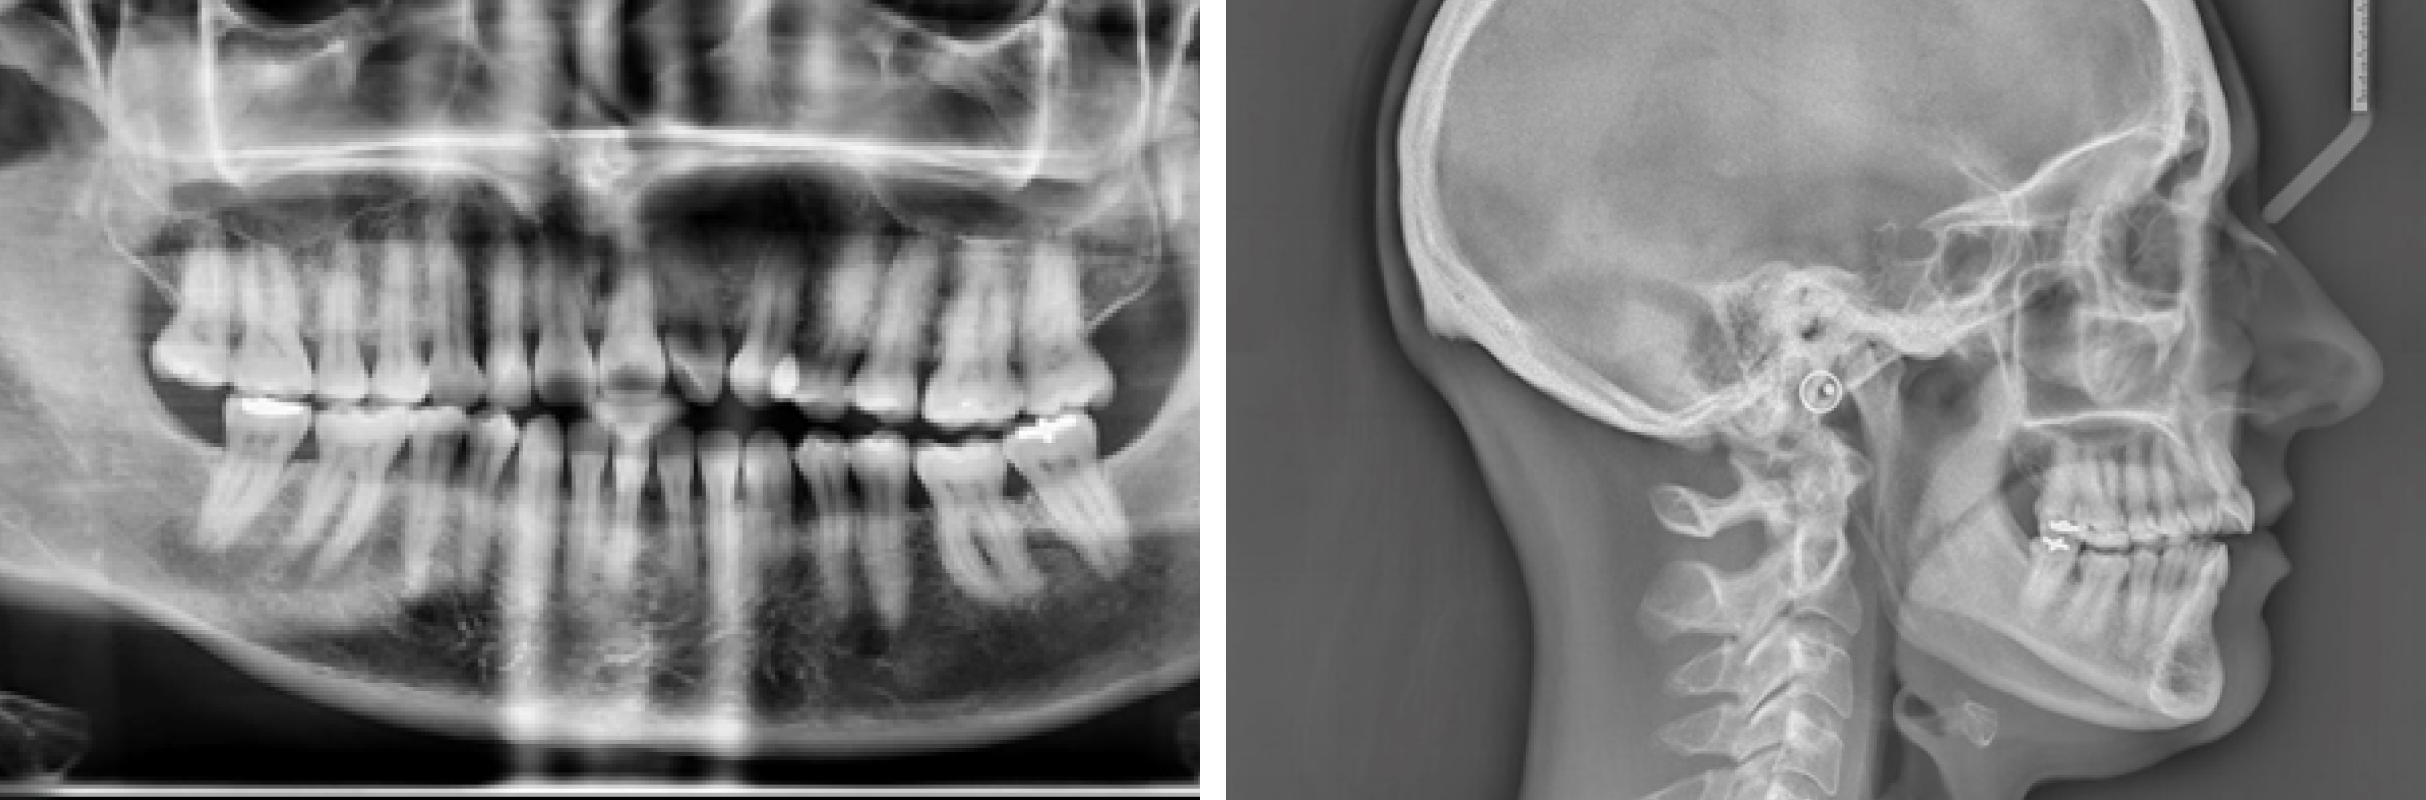

- • Des radiographies